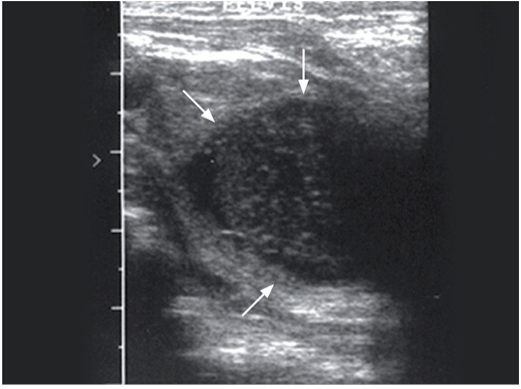

一只七岁未去势暹罗猫患有细菌性前列腺炎并发膀胱炎。超声影像上可见其前列腺位于膀胱尾侧,为一直径3cm的卵圆形团块样结构,内部低回声,外部轮廓回声较高(图11)。